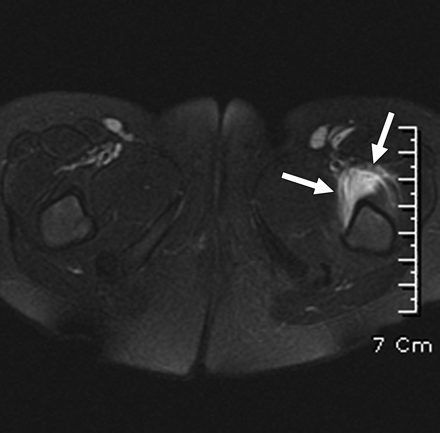

Resonancia magnética

- Un estudio de Lee y cols. propone que se puede diferenciar sinovitis transitoria de artritis séptica mediante resonancia magnética. Este estudio encontró que la artritis séptica presenta alteraciones de la intensidad de la señal en la médula de la cadera afectada. Sin embargo, hacen falta más estudios para confirmar este método de diagnóstico no invasivo (imagen 4).

Imagen 4: Alteraciones de señal en médula ósea observadas en resonancia magnética, compatibles con artritis séptica.